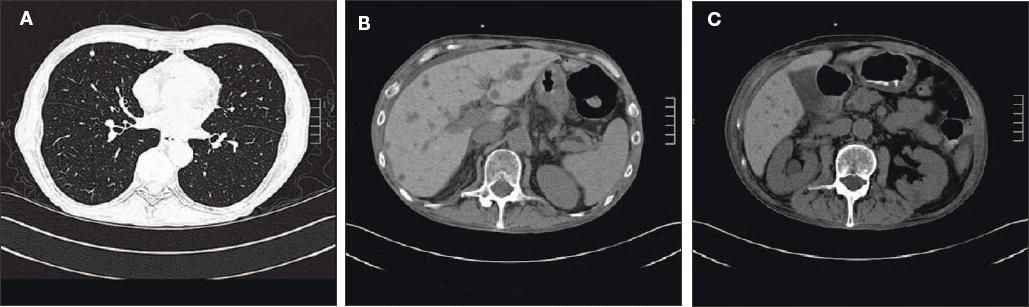

Figure 1 -

A CT scan of the chest (A) revealed multiple 1- to 2-cm nodular lesions typical of a Fusarium infection.A CT of the abdomen (B) and of the abdominal pelvic region (C) revealed multiple hypodense liver and kidneylesions consistent with dissemnated Fusarium infection, which was confirmed by a liver biopsy and urineculture.